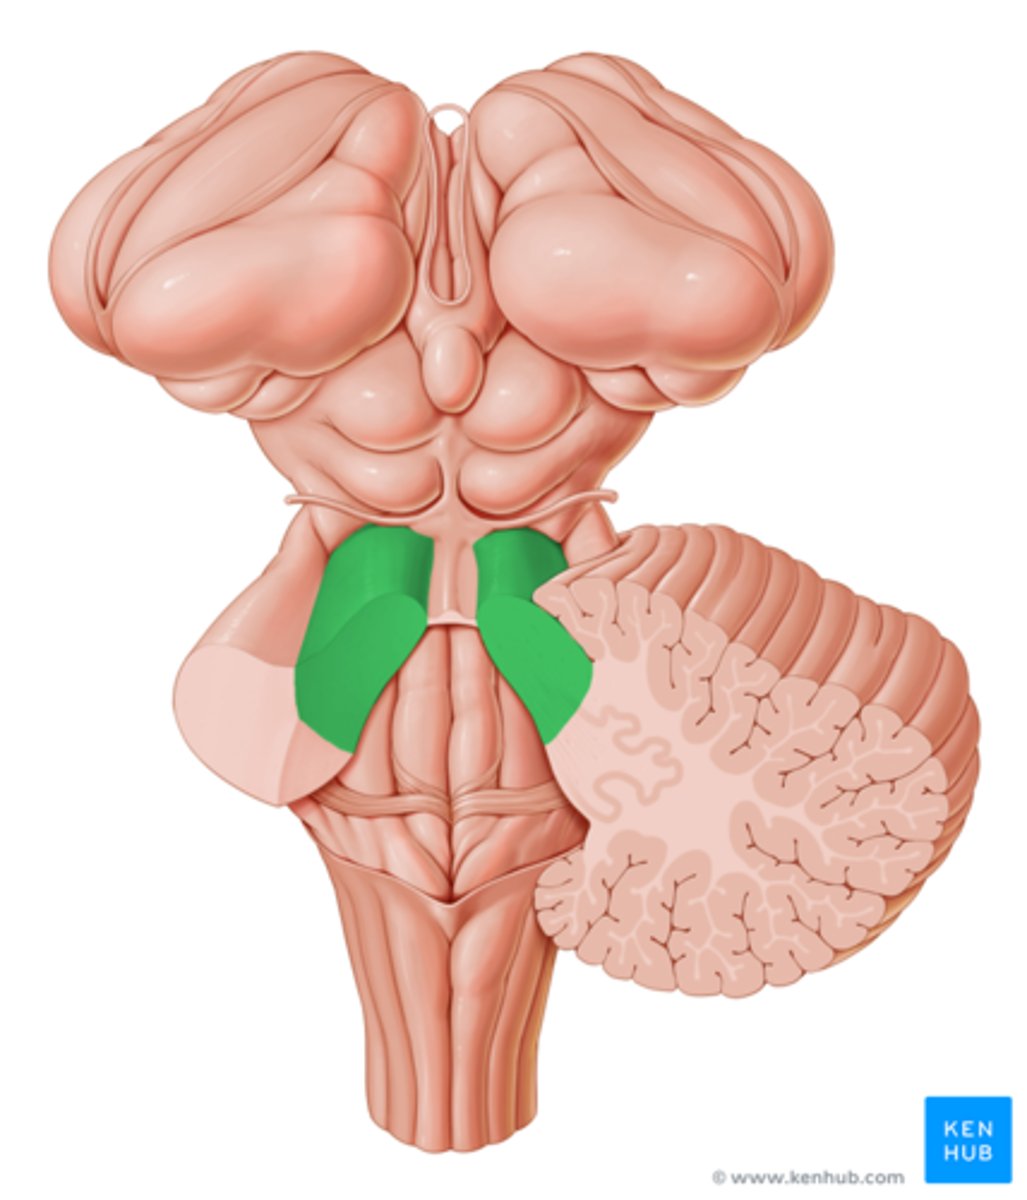

superior cerebellar peduncles

middle cerebellar peduncles

pons

medulla oblongata

pyramids

inferior cerebellar peduncles

cerebellum

right and left cerebellar hemispheres

vermis